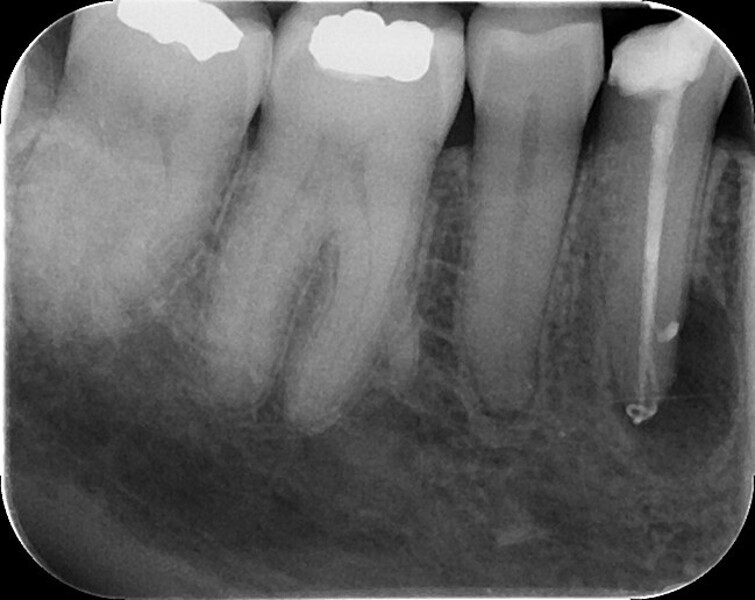

Shaping a Type V mandibular premolar with VDW.ROTATE